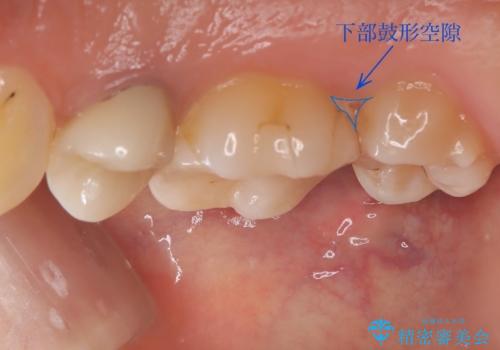

- 元々入っていたセラミックインレーは、6番目と7番目の歯の隙間を無理やり咬合面の近遠心的幅径を伸ばし埋めたような形態で、下部鼓形空隙が広めで食渣が溜まりやすい状態でした。

オールセラミッククラウンの膨隆で下部鼓形空隙を適切な大きさに調整しました。